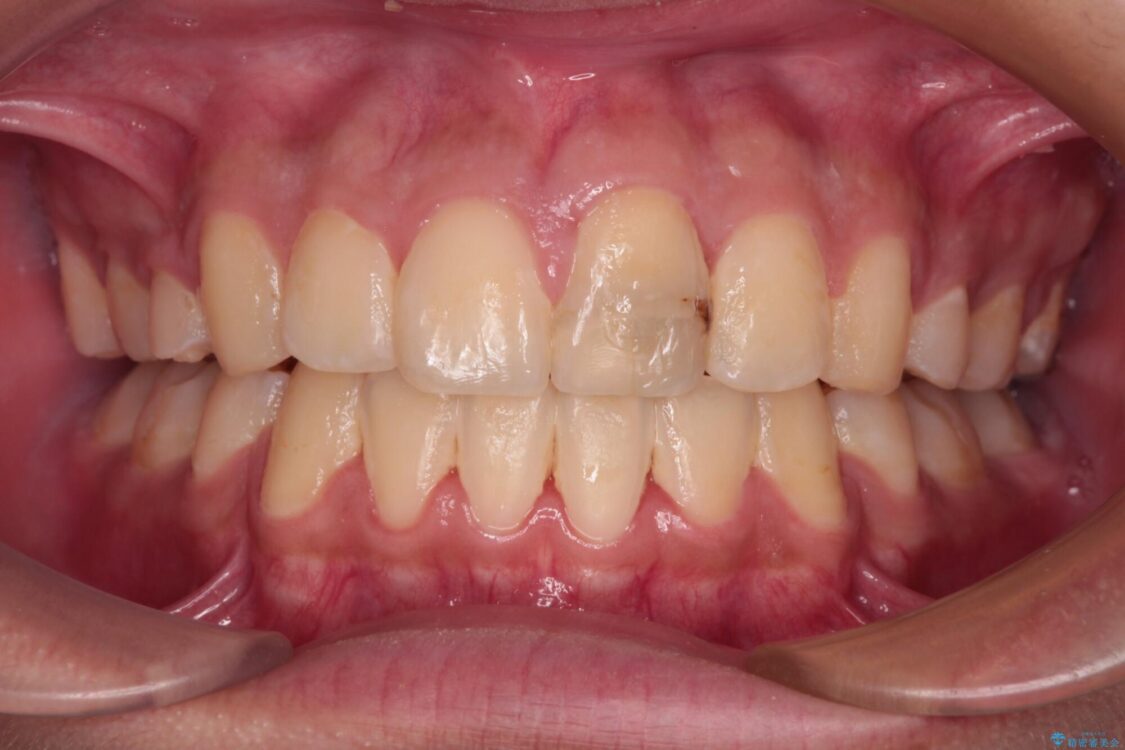

治療後

• 膨らんだ口元 ワイヤー装置での抜歯矯正 治療後画像

小学生の頃に上顎前歯をぶつけ、歯の一部が破損している状態であったので、歯根が歯槽骨と癒着して移動しない可能性がありましたが、無事に治療を終えることができました。